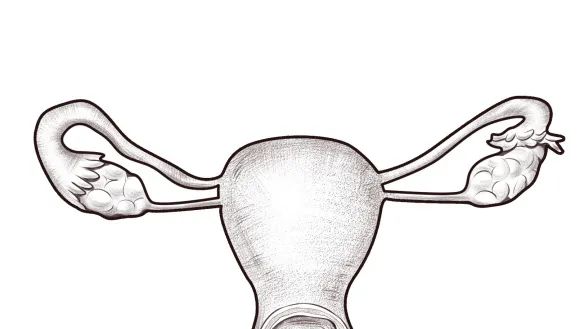

正常的子宫腔是一个类似倒三角或者倒梨形,宫腔也是空空的,是个宽敞的一室户。虽然宫腔有大小之分,但是正常情况下,并不影响生育。

一个宫腔被纵膈分成两个

这在医学上叫子宫纵膈,属于最常见的子宫腔畸形,就是在宫腔的中间多出了一道隔(墙),而且这面墙的长度不一(分为完全纵隔与不全纵隔),厚度也不一样。这一面“墙壁”的存在可能使得子宫腔变狭小。